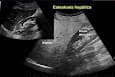

o Porque en la Ecografía, ( Ultrasonidos ), que muestra un hígado “brillante”(producido por el depósito de grasa), y todo ello en una persona que tiene obesidad, o sobrepeso, y /( o diabetes, y /o Alteraciones del colesterol o triglicéridos. Y además que no bebe alcohol en cantidades tóxicas., y en el que el médico no encuentra otra causa de enfermedad del hígado.